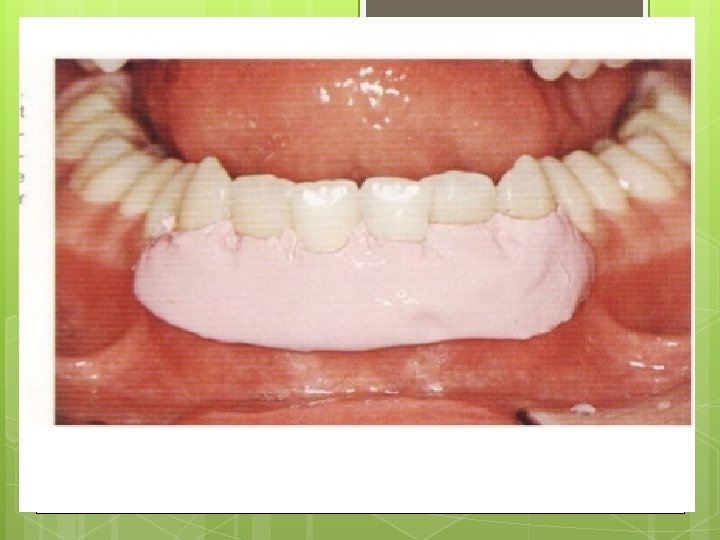

. : 3. Flap retraction

Root planing with direct vision… THE MOST IMPORTANT STEP IN SURGICAL PROCEDURE 5 -Direct root planning